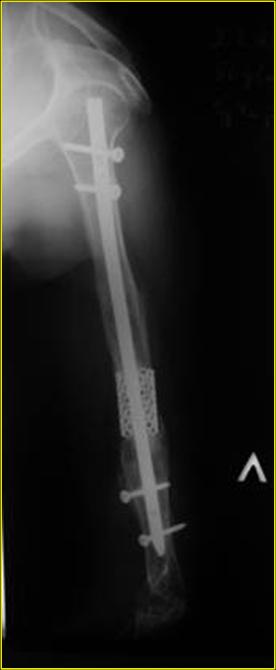

На примере два случая, извиняюсь за качество снимков, снимки и случаи из бывшего союза.

Первая больная с "успехом" была прооперирована 6 раз различными методами открытого и закрытого

остеосинтеза, включая то, что в Кисловодске заезжим австралийским "кудесником" на ложный сустав уложена скорлупа от страусиновых яиц. Последняя операция одиноким локинг плейт в одной из клиник.

Через год по поводу тех же проблем сделали ревизию, оригинальную пластину оставили как есть, только укрепили добавлением еще одной пластины и сделали костную пластику.

Через два месяца увидели признаки консолидации.

Второй случай, также после множественных операций:

пластина, аппарат, серкляж и парез нерва.

Также ревизия, из-за низкого состояния доступ был

сделан через остеотомию локтевого отростка.

Ложный сустав фиксирован двумя локинг плейт с

аутокостной пластикой, также через два месяца увидели признаки консолидации.

Движение в суставе разрешили в две недели.